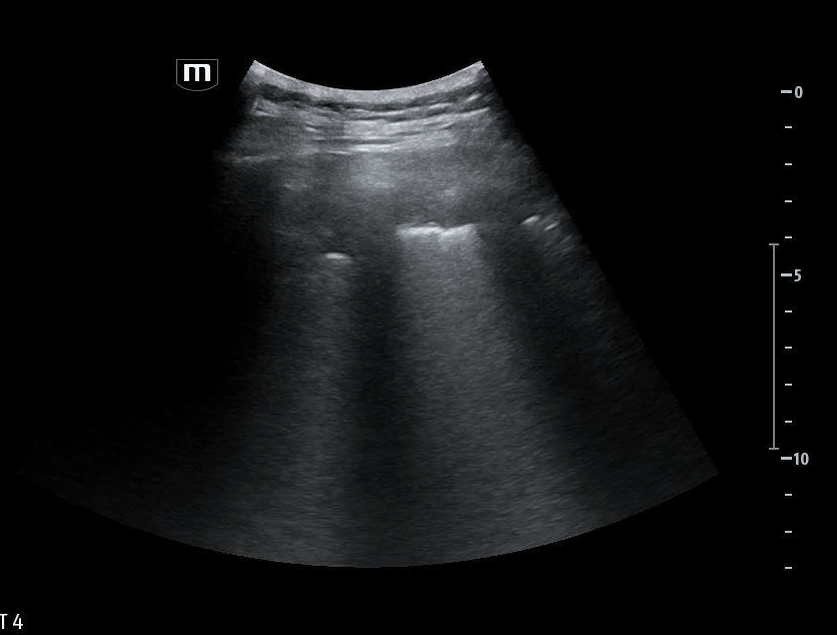

Additional ultrasound imaging are obtained:

Image 3 demonstrates the expected location of the parasternal long-axis (PSL) view; however, the PSL view is notably absent at the left sternal border.

Image 4 instead reveals cardiac activity visualized to the right of the sternal border, suggesting mediastinal shift.